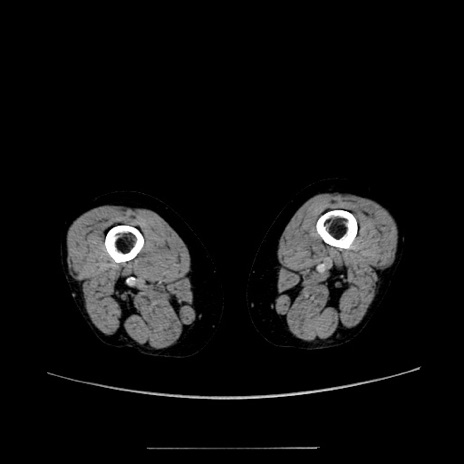

冠状断像

【症例】70歳代女性

【主訴】お腹が張る

【現病歴】1週間くらい前から腹部膨満の自覚あり。昨日夜から増悪したため、本日救急外来受診。

【身体所見】意識清明、BT 36.5℃、BP 165/106mmHg、HR 80bpm、SpO2 98%、腹部:膨満、軟、自発痛・圧痛なし、触診にて不快感あり、腸蠕動音:減弱

【データ】WBC 12600、CRP 1.04